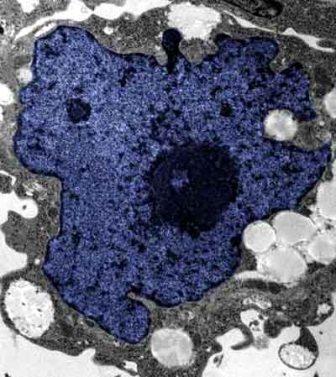

在成人體內(nèi)及胚胎內(nèi)發(fā)現(xiàn)的干細(xì)胞屬于主細(xì)胞,能發(fā)育成各種各樣的組織,可作為人體“修補(bǔ)工具箱”,取代死去及腐壞細(xì)胞組織。此前,最可行的干細(xì)胞為胚胎干細(xì)胞,但它的使用一直受到爭(zhēng)議,因?yàn)橐谂咛コ槿「杉?xì)胞會(huì)令胚胎死亡,有人認(rèn)為這樣是變相奪走一條生命。

來(lái)自英國(guó)和加拿大的兩組研究員所用的新方法不必使用病毒。這項(xiàng)新突破暗示科學(xué)家現(xiàn)在能更認(rèn)真地看待在醫(yī)學(xué)中利用皮膚干細(xì)胞(即誘導(dǎo)多功能干細(xì)胞,俗稱“iPs”細(xì)胞)的前景。

這些細(xì)胞只要配以適當(dāng)?shù)幕瘜W(xué)品和蛋白質(zhì),就能轉(zhuǎn)化成腦神經(jīng)元、制造胰島素的胰腺細(xì)胞、骨或軟骨、心臟肌肉,或其它多種組織。這些細(xì)胞利用病人皮膚來(lái)培育,更暗示它們不會(huì)被人體排斥。